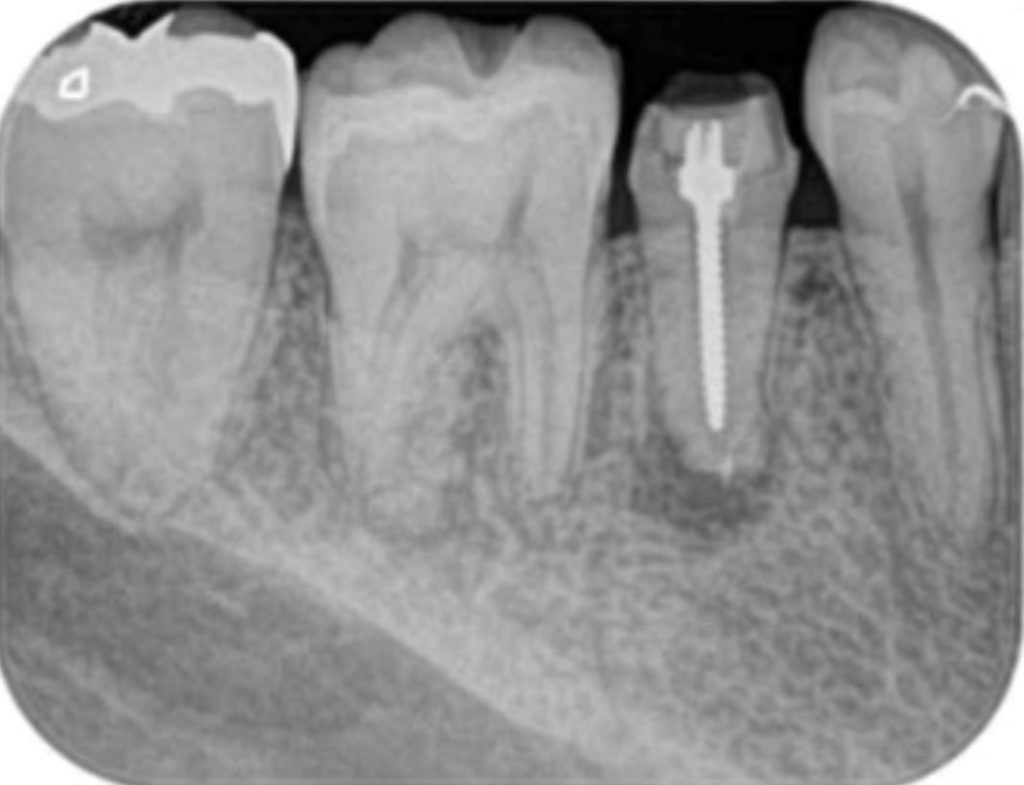

術前(長い金属の棒を取る+感染を治すために紹介された)

術後(長い金属の棒はマイクロスコープ下で安全に除去し薬を詰めた状態。わずかに画像が変化し治癒してきている)